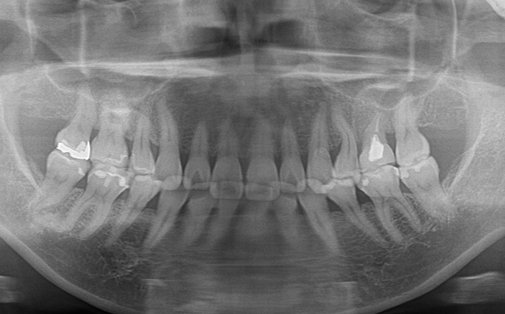

抜歯した親知らずを移植(3)

Before

After

左上の歯が折れています。折れた歯を抜き、親知らずの歯を移植しました。